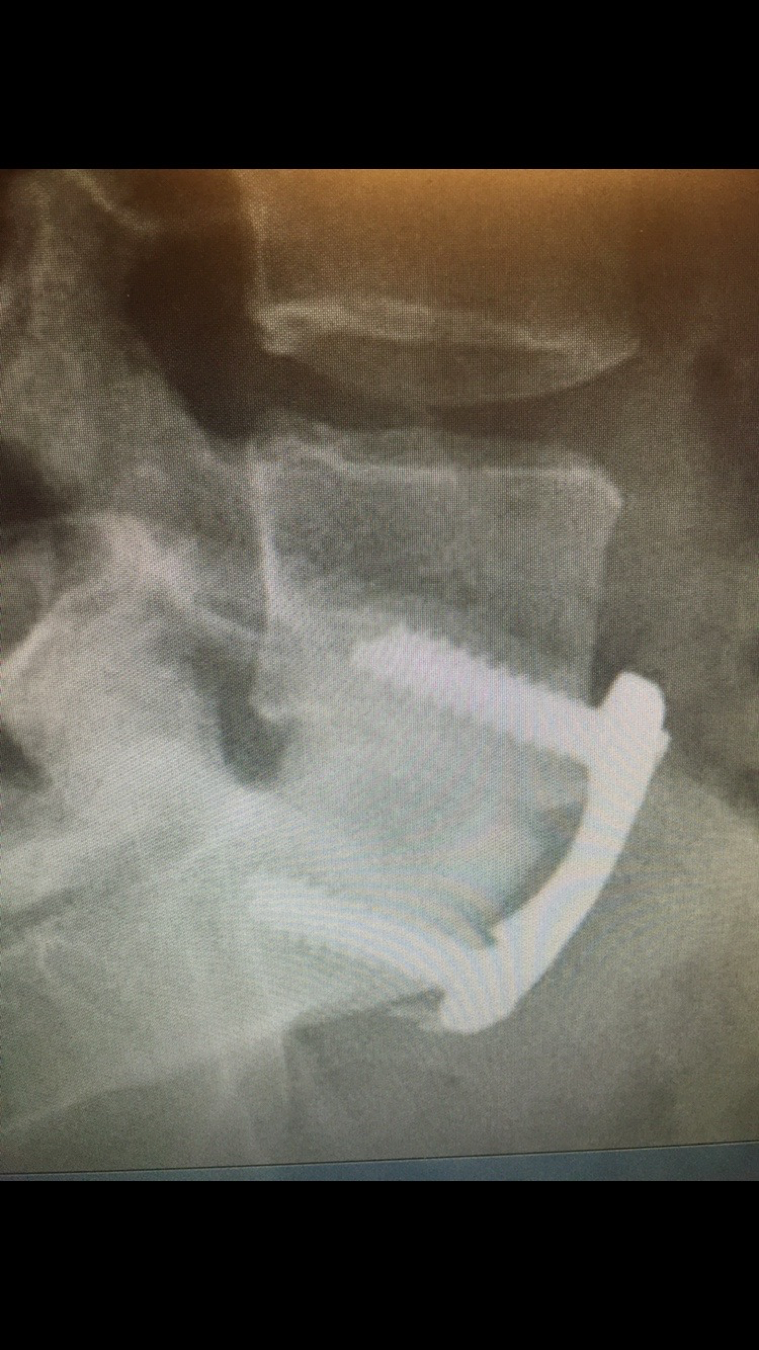

Below is the MRI of a 30 year-old female with severe right leg pain due to a right L5-S1 herniated disk. She failed 8 weeks of conservative care, including physical therapy, anti-inflammatory agents, and epidural steroids. She underwent outpatient microscopic lumbar discectomy, and had complete relief of her leg pain immediately. She has returned to high level sports.